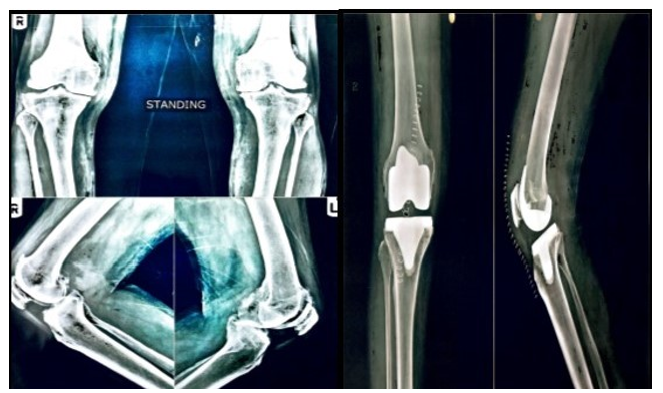

6. Knee Replacement Surgery

Health and Care Foundation offers very low-cost or free total knee replacement surgery to those who are financially disadvantaged and do not have a PMJAY card or Health Insurance Policy to enable them to lead dignified lives within the community.

Surgeries

125